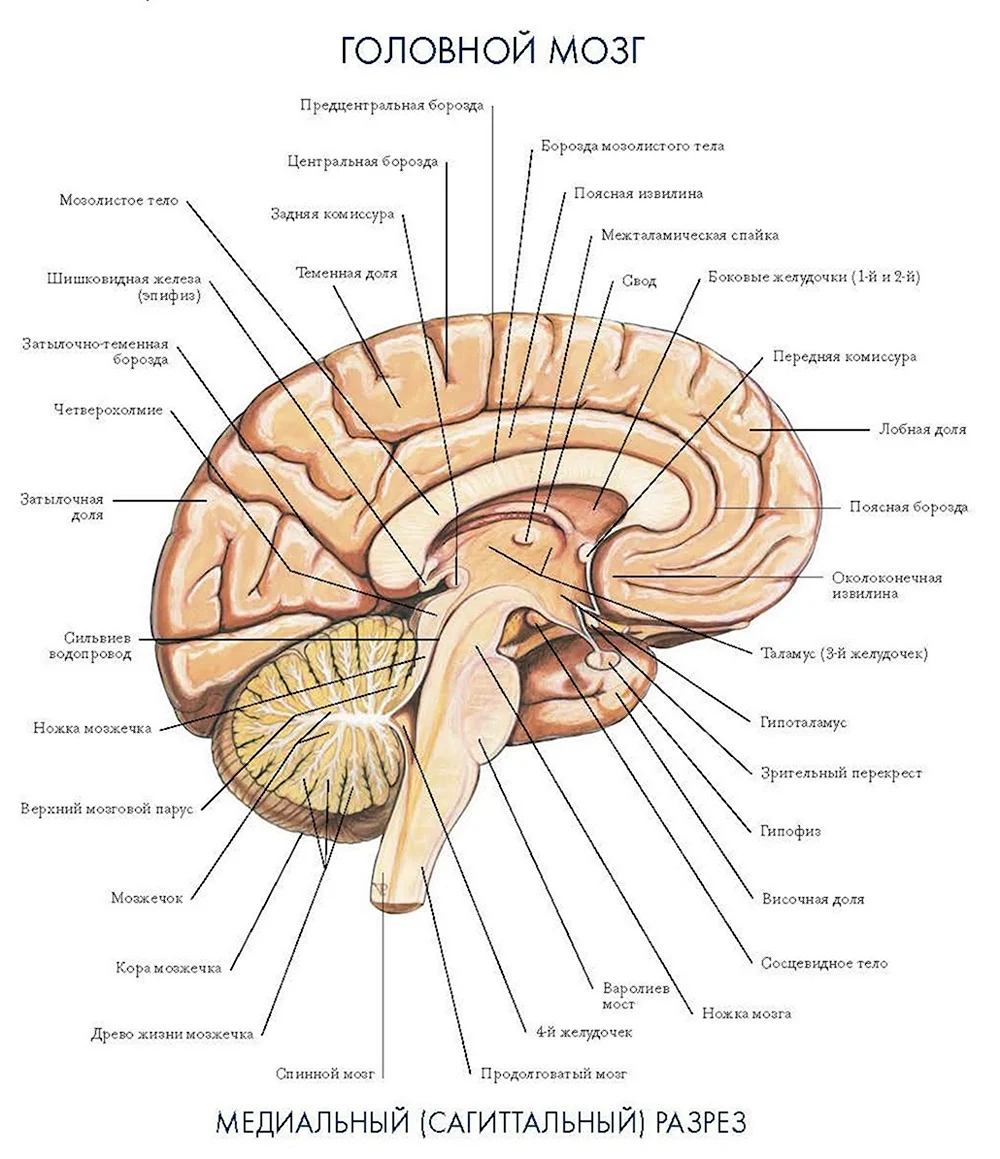

Легкие рисунки головного мозга: Пошаговые инструкции

Раздел: Житейские мотивы